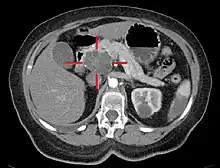

Axial CT image with IV contrast and added color. Cross lines towards top left surround a macrocystic adenocarcinoma of the pancreatic head.

Medical imaging techniques, such as computed tomography (CT scan) and endoscopic ultrasound (EUS) are used both to confirm the diagnosis and to help decide whether the tumor can be surgically removed (its "resectability").[12] On contrast CT scan, pancreatic cancer typically shows a gradually increasing radiocontrast uptake, rather than a fast washout as seen in a normal pancreas or a delayed washout as seen in chronic pancreatitis.[50] Magnetic resonance imaging and positron emission tomography may also be used,[11] and magnetic resonance cholangiopancreatography may be useful in some cases.[30] Abdominal ultrasound is less sensitive and will miss small tumors, but can identify cancers that have spread to the liver and build-up of fluid in the peritoneal cavity (ascites).[12] It may be used for a quick and cheap first examination before other techniques.[51]